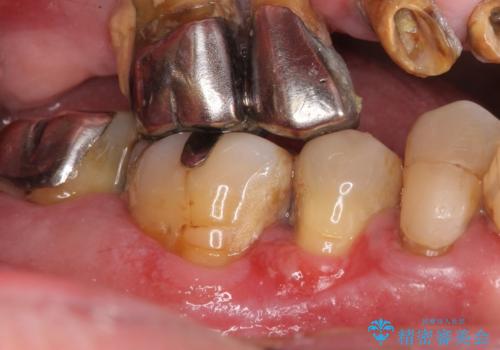

- 全顎的な重度歯周病の患者様です。

骨吸収の進行している右下臼歯部に、再生療法(骨を増やす手術))を行いました。

埋伏していた親知らず、保存不可能な右下の一番奥の歯(右下7)、状態の悪い犬歯(右下3)は抜歯しております。